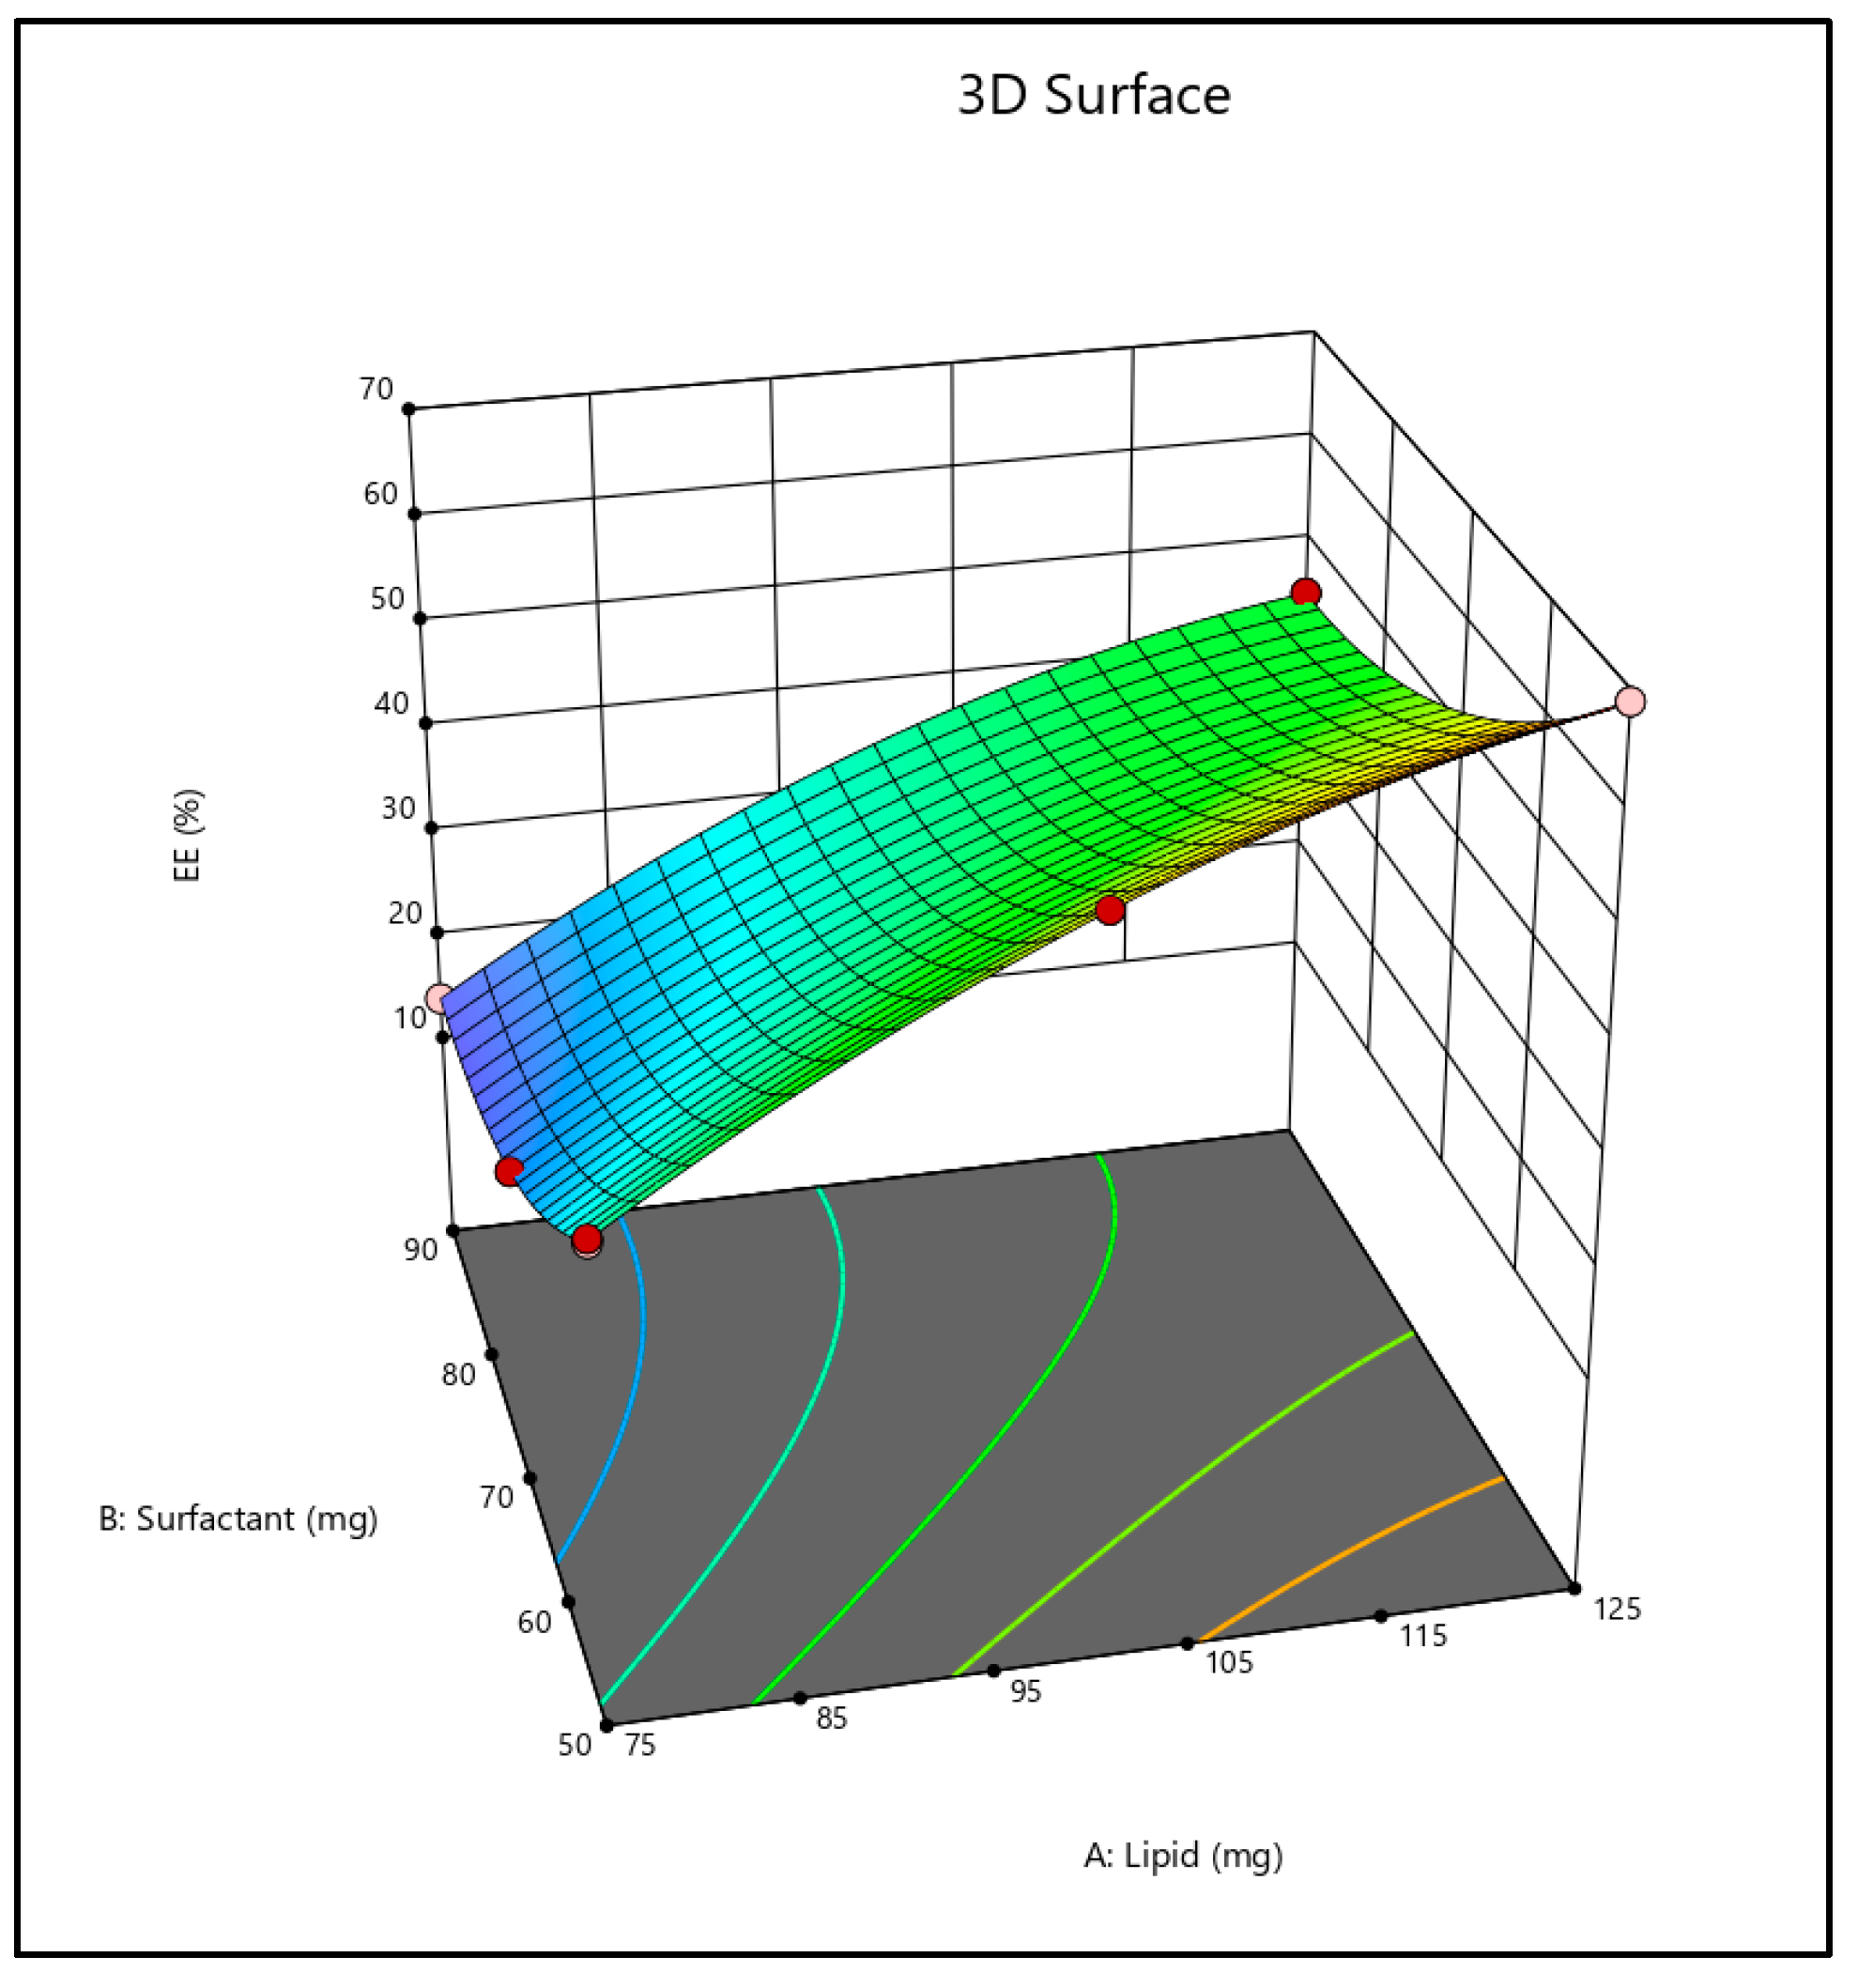

2.3. Effect on Entrapment Efficiency

2.4. Optimization of Formulation

3.2.2. Experiment Design for Optimization

3.2.3. Optimization of the Formulation